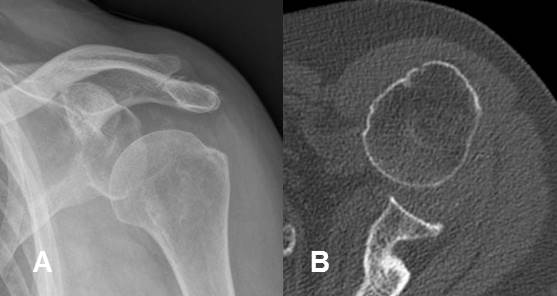

Fig 158. Luxación glenohumeral.

A: Rx AP. Luxación glenohumeral anterior.

B: TAC axial. Se confirma la luxación. Adicionalmente hay un fragmento libre intra-articular.